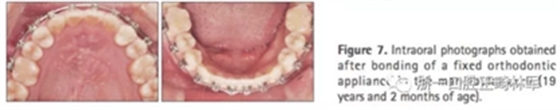

第三階段(圖7,表2)

19歲2月時行固定矯治排齊下頜牙列建立穩(wěn)定的咬合及正常的覆合覆蓋,持續(xù)1年10月。摘除后(21歲)上下頜用固定保持器,上頜牙弓用Hawley保持器。